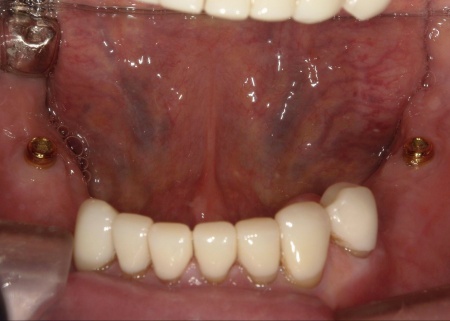

次に、上下左右の奥歯部に1本ずつ、左上前歯に1本、計5本のインプラントを埋入する手術を行いました。

根管治療が終了した上の歯には、オーバーデンチャーの支えとなる内冠(入れ歯を安定させるための土台)を、インプラント部分にはロケーター(義歯をしっかり固定するための連結装置)を装着しました。

この仕組みにより、必要に応じて入れ歯の取り外しを可能にしながら、日常生活では安定した状態を保つことができます。

また、上顎は残存歯が少ないためすべてを覆う総入れ歯で、下顎は前歯がしっかり残っているため部分入れ歯の形で作製しました。

完成した入れ歯を装着していただき、噛み合わせや義歯の安定性、見た目の仕上がりに問題がないことを確認して、治療を終了しています。